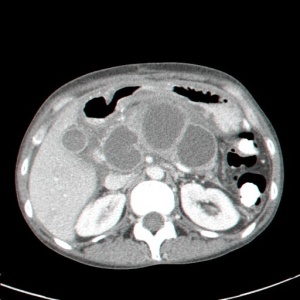

- טומוגרפיה ממוחשבת – נראה באיזור הלבלב גוש או גושים בד"כ בעלי גבולות ברורים המכילים בתוכם נוזל (תצלום 3.9).

| תצלום 3.9: כיסיות מדומות מרובות (חץ) באיזור הלבלב בשני חתכי CT. | |